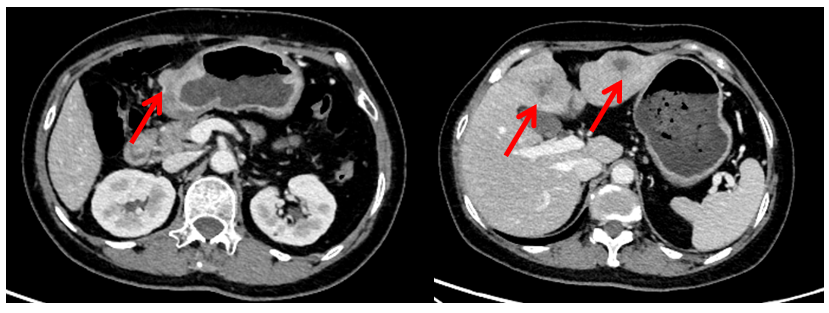

CT:胃窦壁不规则增厚,较厚处约2.2cm;肝左叶见数个结节、肿块影,大者位于肝左内叶,约3.5*3.5cm(图1)。

MRI:胃窦壁不规则增厚,较厚处约2.4cm;肝门部、腹膜后多个淋巴结显示,大者短径约1.5cm;肝内多发转移,大者约3.9*4.0cm(图2)。

图2. 腹部MRI检查